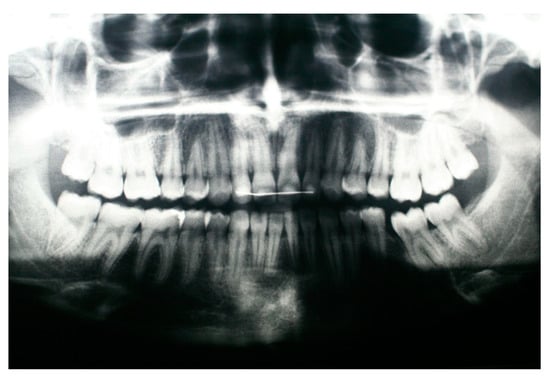

2. Case Presentation